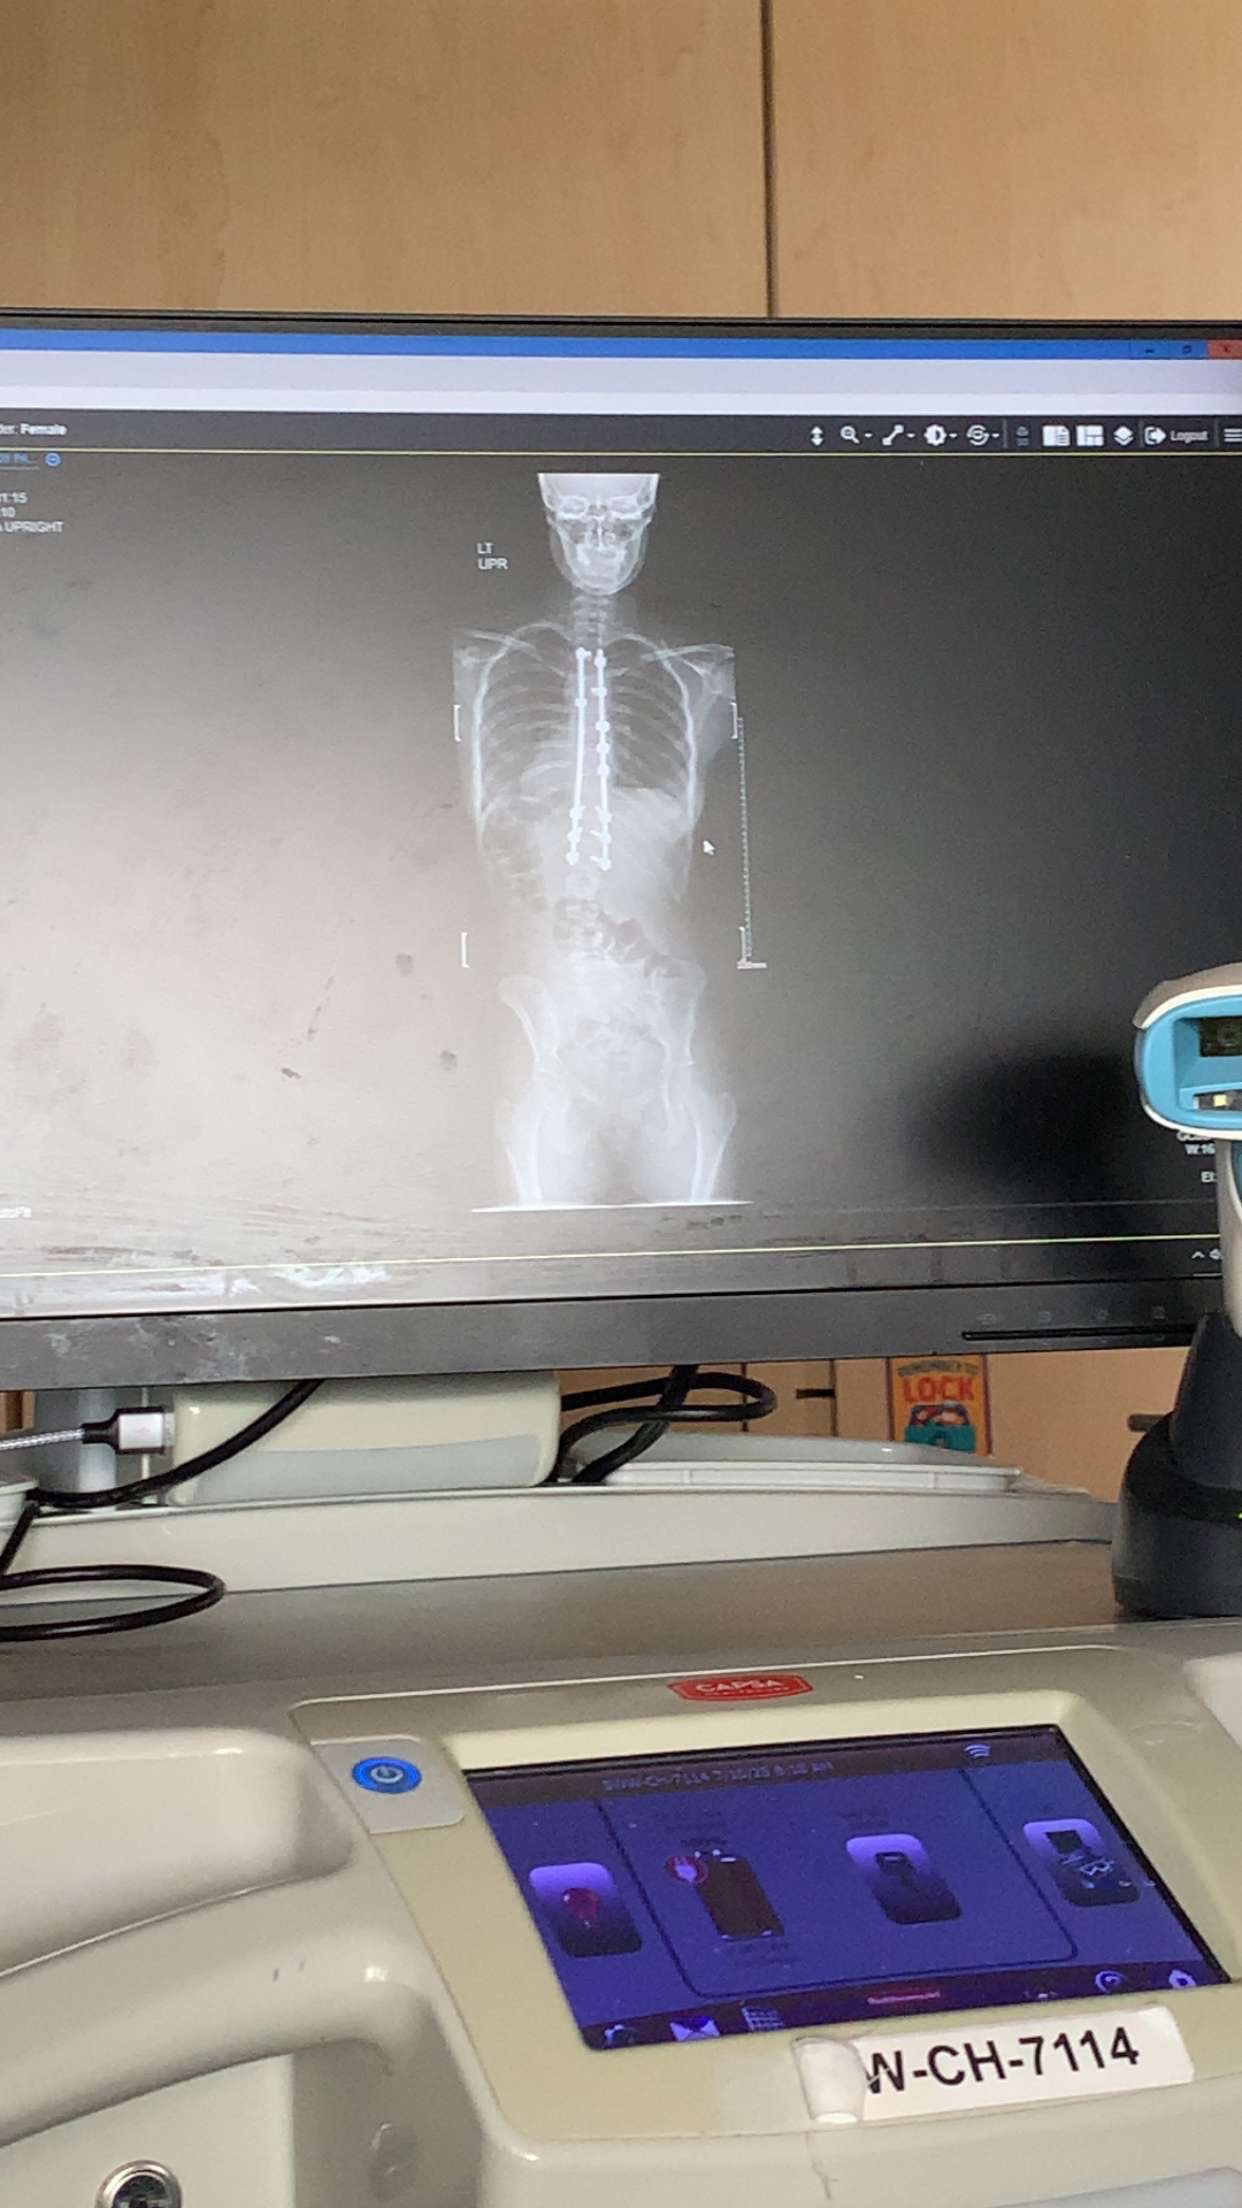

My daughter is 16 years old and has severe scoliosis. I'm raising funds to help get through her recovery as she had to have back infusion surgery. It's been a rough road and she has a long recovery ahead, but she's staying strong and would really appreciate any help she can get.